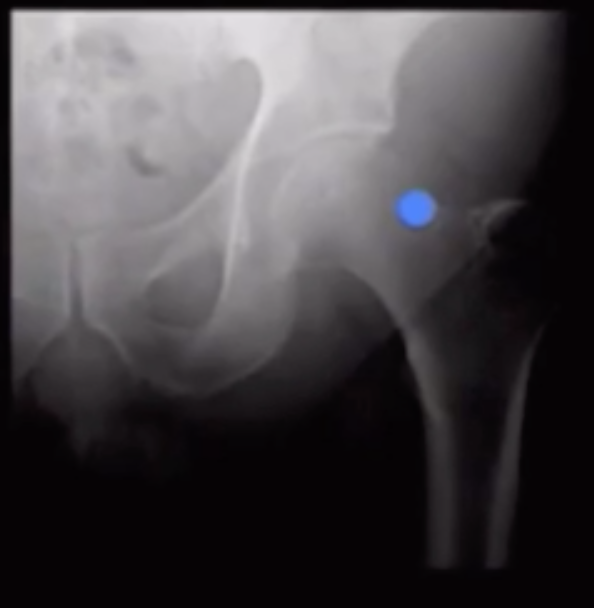

Arthrogram Hip

• Cocktail ~15 cc

• MRI

• 0.1 cc gadolinium

• 5 cc omnipaque

• 15 cc saline